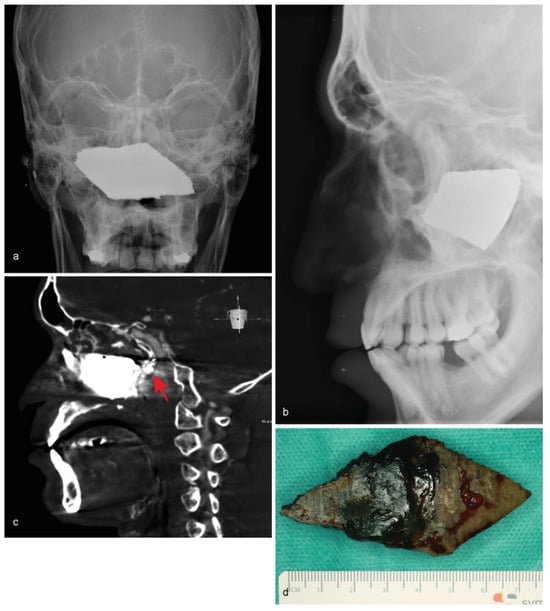

Figure 4. (a) Intraoperative C-arm radiograph showing destruction of the ethmoidal bone with opacity, as well as a radiopaque intracranial foreign object close to the occipital bone. (b) Postoperative image of the removed bullet.

• Case 4: Another case of a foreign body caused by a gunshot was presented by a 63-year-old patient. Clinically, a single entry wound was detectable in the forehead, but there was no bullet exit wound. An MDCT scan revealed a single bullet close to the occipital bone, which had entered the cranium through the forehead, crushing the frontal sinus and ethmoid cells (Figure 4a). A bullet with a 2-cm diameter was removed by craniotomy in cooperation with colleagues from the neurosurgery department (Figure 4b). Wound therapy included debridement with large exposure of the frontal sinus, reconstruction and fixation of the anterior wall, and dura repair under a perioperative antibacterial regime. Shortly after removal, the patient was transferred to begin neurological rehabilitation.